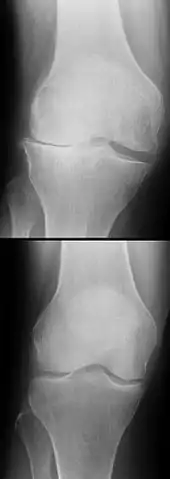

L'évolution à long terme du genou être commence à bien connue dans le cas des ligamentoplasties, faisant apparaitre un haut niveau de satisfaction subjective à plus de 20 ans chez la majorité des patients, une stabilité antéro-postérieure et rotatoire normale dans 90% des cas, mais aussi une augmentation de signes d'arthrose (concernant surtout les patients ayant eu des lésions cartilagineuses ou méniscales concomitantes), ainsi qu'une altération durable de la proprioception[130],[131]. En revanche, on ne dispose pas d'études à 10 ans ou plus ni pour les protocoles récents de cicatrisation avec attelle, ni pour les toutes dernières techniques de suture chirurgicale[102].

Dans les années 1970 à 1980, la limite d'âge pour les opérations de reconstruction du LCA se situait environ à 35 ans. Ceci était dû aux possibilités opératoires encore restreintes en raison de la difficulté d'approvisionnement en sang et des mauvaises perspectives de guérison des LC. Aujourd'hui, il n'y a plus de limite d'âge[166]. L'état du genou, les souhaits du patients et sa motivation sont les facteurs essentiels pour la décision d'opérer ou non. Dans la plupart des cas, du point de vue médical, il n'y a pas besoin d'intervention chirurgicale immédiate pour une rupture de LC. Une rupture récente n'est opérée dans l'idéal qu'après six à huit semaines de physiothérapie ou kinésithérapie. Le genou a alors normalement perdu complètement son épanchement articulaire[167]. Dans de nombreux cas, l'opération a lieu plusieurs mois, voire années après la rupture du LC. Par exemple, on la pratique quand une instabilité du genou d'abord faible conduit à des douleurs pour le patient[167]. Dans les pays scandinaves, Norvège, Danemark et Suède, les temps moyens entre la rupture et l'opération sont respectivement de 7, 9 et 10 mois[168], par contre aux États-Unis c'est 2,4 mois. Les quartiles sont de 1,2 et 7,2 mois aux États-Unis, et de 4,2 et 17,8 mois en Norvège[37].